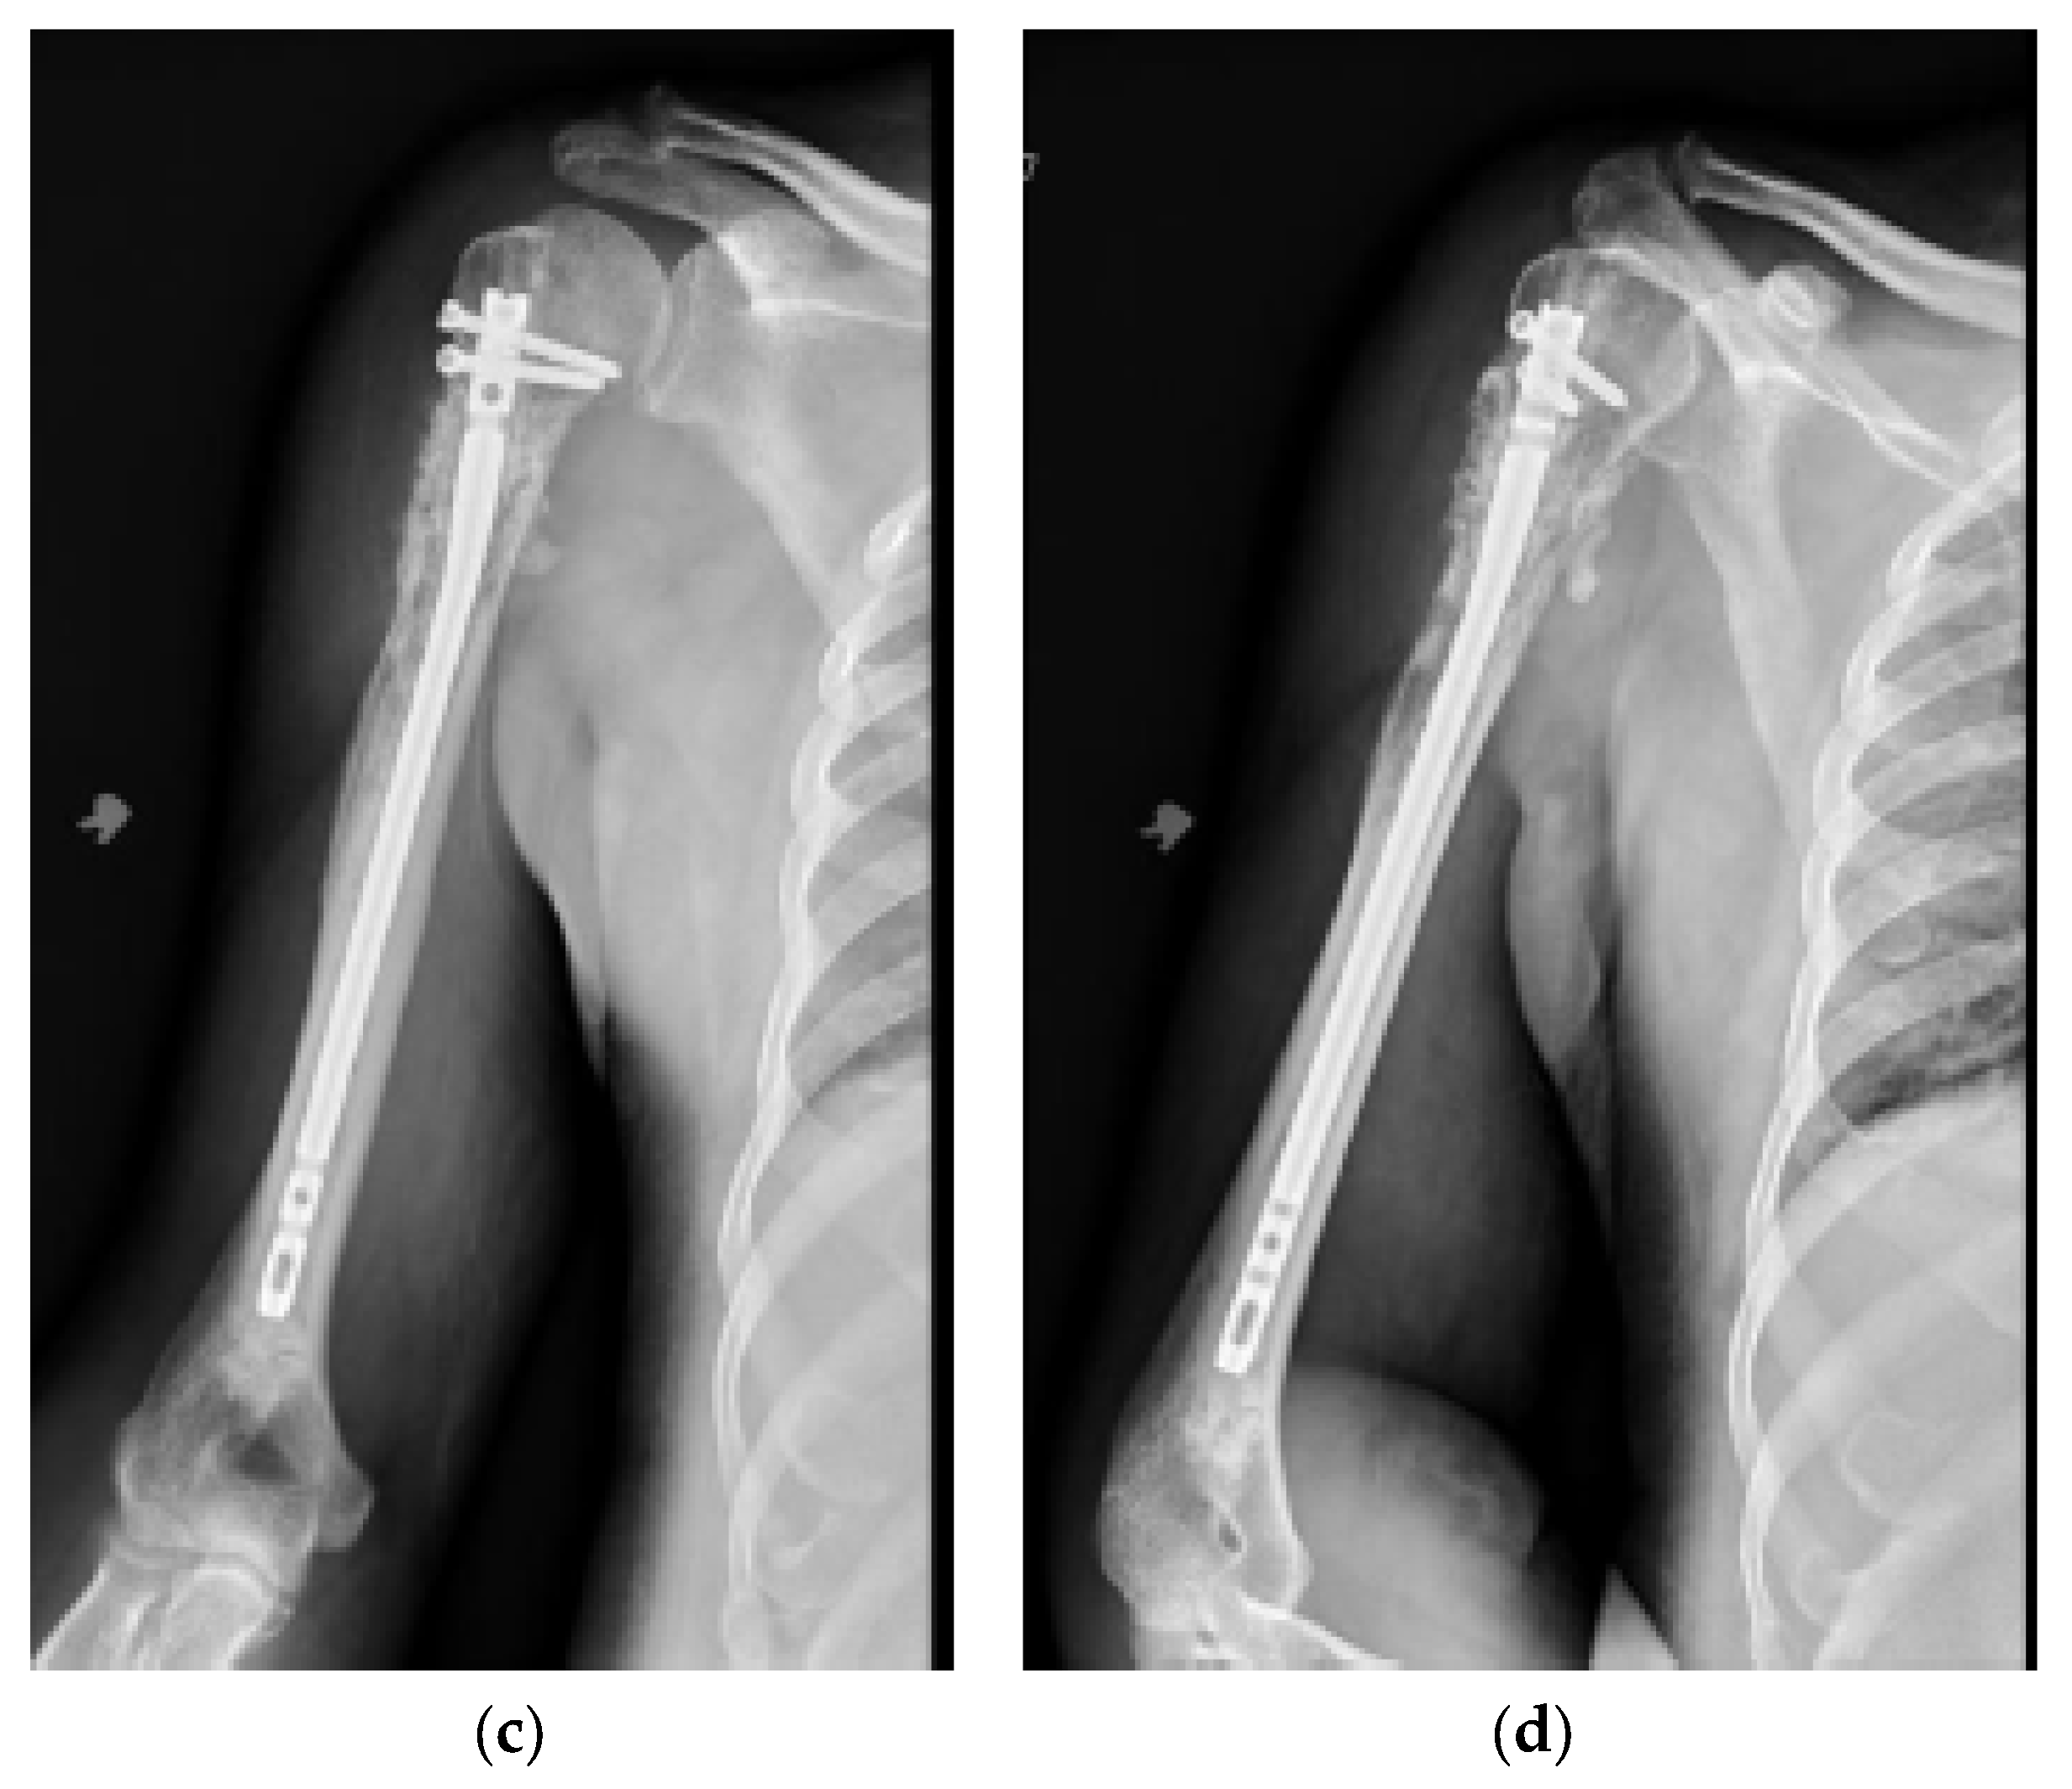

The surgical technique is detailed in Supplement S2 [44]. All surgeries were conducted with a minimally invasive technique, except for 7 pathologic fractures that required direct tumor site opening (curettage resection for radioresistant tumors and/or significant bone defects [5 cases], as well as failure to obtain acceptable fracture closed reduction [2 cases]). There were 3 patients who received plate fixation, in addition to intramedullary nailing, for extensive periarticular bone involvement. In addition, one patient in the cemented cohort required intraoperative conversion from a nail to a plate construct due to a proximal nail cutout of the lateral cortex. This patient was excluded from functional score analysis, but they were included in survival and complication analyses. The postoperative rehabilitation protocol was similar for all patients. An arm sling was given for initial postoperative comfort, and immediate range of motion, starting with pendulum exercises, was allowed. Weight bearing depended on bone involvement and fixation stability, but activities of daily living were allowed immediately. After discharge, outpatient visits were scheduled at 2 and 6 weeks postoperatively, every 3 months for the first year, every 6 months for the second year, and once a year afterwards. Radiographs were obtained immediate postoperatively, at 3 months, and at every subsequent visit (Figure 2 and Figure 3). In most patients, chemotherapy and/or radiation (3000–3500 Gy) were started/resumed 10 to 21 days after their index surgery, as deemed appropriate by the multidisciplinary team.

Figure 2.

(a) AP and (b) lateral right humerus radiographs of a 67-year-old male with a mixed lytic sclerotic lesion in the proximal meta-diaphyseal region, with a pathologic fracture from a newly diagnosed metastatic prostate cancer. This was treated by a bone biopsy, followed by a cemented IMN with two proximal inter-locking screws and no distal screw, as shown in the (c) AP and (d) lateral humerus radiographs. Cement was used for augmentation, due to poor proximal humerus bone quality, to support the nail and the inter-locking screws.

Figure 3.

(a) AP and (b) oblique left humerus radiographs of a 47-year-old female with mixed lytic sclerotic lesion in the proximal meta-diaphyseal region, with a pathologic fracture and periosteal reaction in a patient with established metastatic breast cancer. This was treated by an uncemented IMN, with three proximal locking screws and one distal screw, as shown in (c) AP and (d) oblique humerus radiographs. No cement was used, as there was enough proximal and distal bone to support the nail and the inter-locking screws, and some healing changes were already evident.